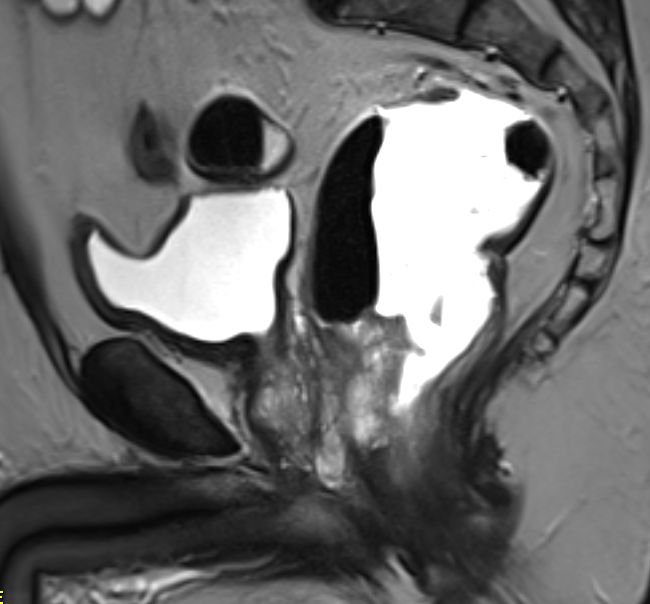

![]() 62-jähriger Mann mit einen Rekumkarzinom der Vorderwand unmittelbar oberhalb der Anokutanlinie. Das MRT zeigt einen Tumorzapfen im Sphinkter ani und eine Infiltration der Samenblasen | ||